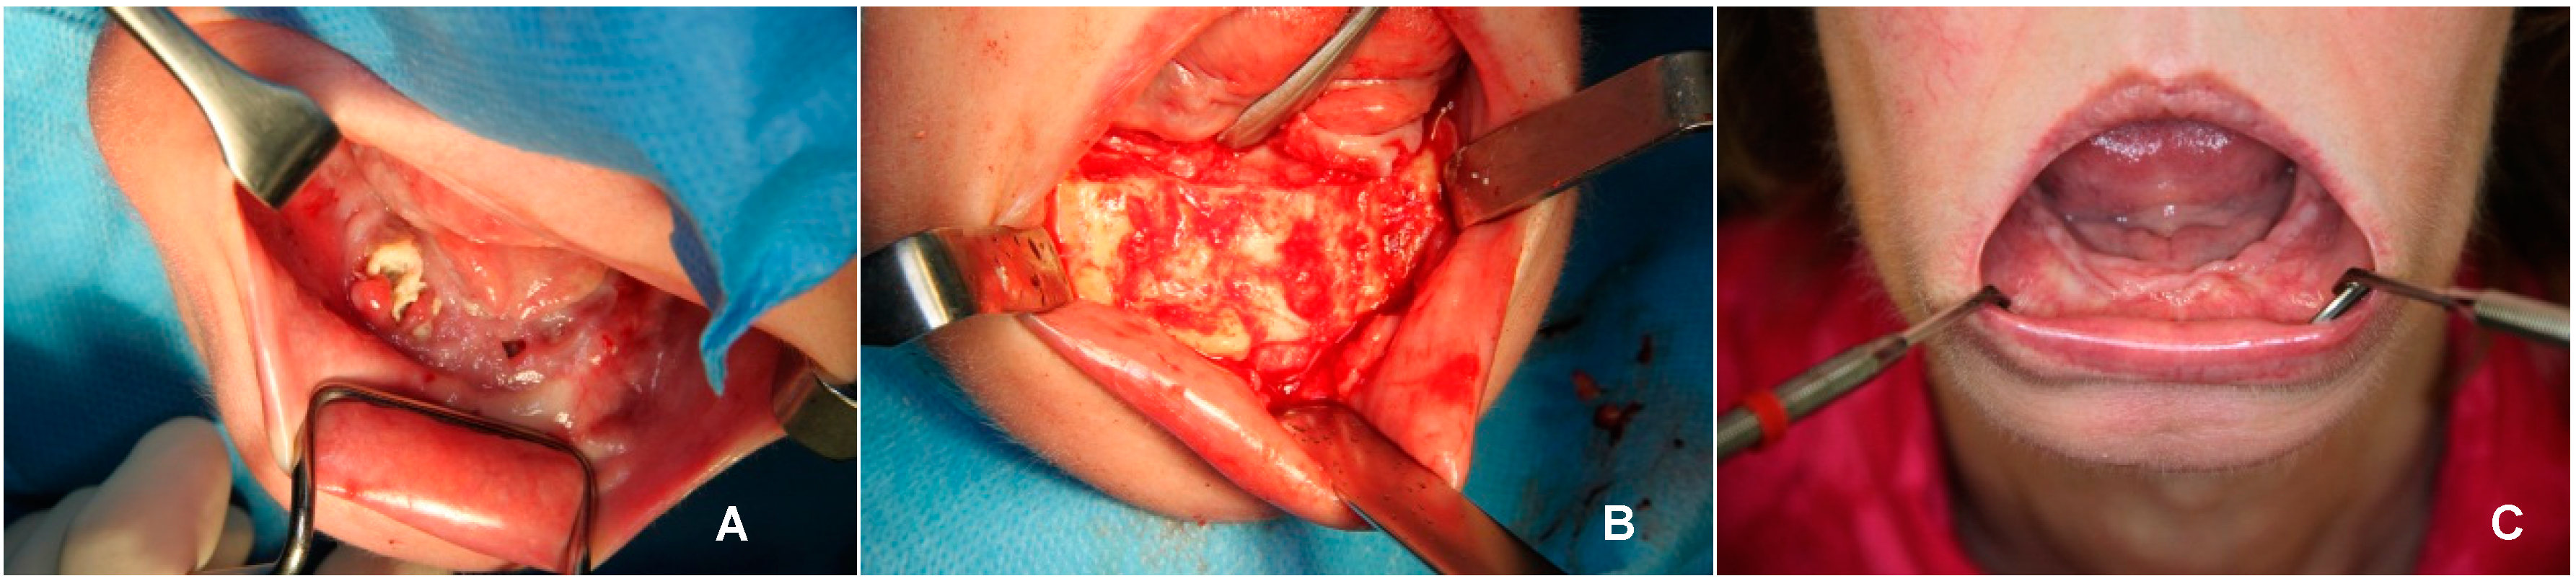

Figure 1.

Photographs before, during and after surgery. (A) Multiple intraoral fistula and denuded bone; (B) Subperiosteal bone before closure of the surgical wound; (C) Intraoral view six weeks after surgery with closed mucosa.

At the presentation of pain, intraoral fistulas (Figure 1A) and an extraoral fistula in the submental region were found. Two months before, she had extractions of all her teeth under general anesthesia elsewhere because of caries and periodontitis, a productive submental fistula, and pain. Afterwards, she had an antimicrobial treatment for 10 days of Augmentin 625 (amoxicillin and clavulanic acid) and Perioaid mouth rinse. Despite the extractions, the pain and the fistulas persisted.

A diagnosis of bisphosphonate-related osteonecrosis of the jaw was made. The patient was treated according to a protocol reported earlier by Alons [4] with a sequestrectomy under general anesthesia in combination with intravenous antibiotics. During surgery, the original mandible from region 34 to 45 appeared to be completely necrotized and sequestrated. The mental nerve could not be identified on the right side, and on the left side it could be identified. When the sequestrae were removed, a large quantity of subperiostal bone was found around the defect, especially at the former lingual border of the mandible. This subperiosteal bone seemed vital and perfused. After partial removal, its buccal shape was lowered and rounded off. Finally, the subperiosteal bone was shaped in order to make a primary closure without dead space possible and it seemed to have sufficient thickness to provide continuity of the mandible (Figure 1B). The wound was closed primarily in layers. The patient received an antimicrobial treatment according to protocol (Penicillin G (6 × 1 million EH) and Metronidazole (3 × 500 mg) were administered for five days intravenously, followed by Amoxicillin orally 3 × 500 mg for three weeks and Metronidazole 3 × 500 mg for three weeks).

The patient’s recovery was good without further complaints, intraoral dehiscences or fistulas (Figure 1C). During follow-up, no pathological fracture of the subperiosteal bone occurred. The panoramic radiograph showed continuity of the mandible and a cortex-like structure. The CT scan six weeks after surgery showed a lingual neo-cortex of the mandible without any signs of resorption (Figure 3B). At follow-up after nine months, the patient was still free of complaints.